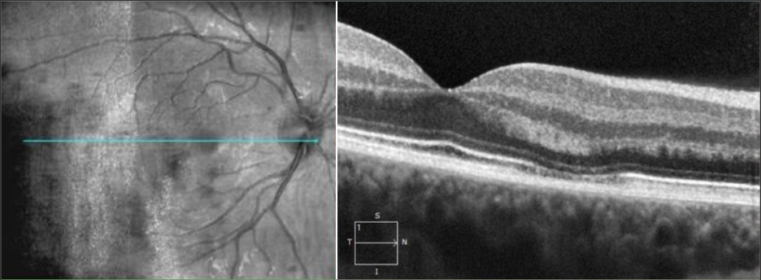

OCT image shows hyperreflective area between the outer plexiform and outer nuclear layer. Images courtesy of Dr. Stephen O'Connell

- SD-OCT: Hyperreflective plaque is seen initially at outer nuclear (ONL) and outer plexiform layers of OCT, indicating disruption of photoreceptor cell bodies and their axons. Focal ellipsoid zone (EZ) disruption ensues. With time, EZ reconstitutes but persistent interdigitation zone disruption is noted. The hyper-reflective plaque fades away and is replaced with ONL thinning.

- A hypereflective plaque between the outer plexiform and outer nuclear layers.

- Disruption of ellipsoid zone/interdigitation zone

- In late stage, thinning of the outer nuclear layer may be seen